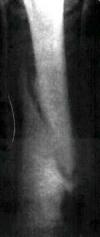

Рис.1 Зона перелома через 35 суток после травмыОбщеизвестно, что исход лечения крупных животных с переломами больших трубчатых костей неблагоприятный или весьма осторожный. Данный же случай связан с терапевтическими действиями при лечении лошади с закрытым переломом плюсневой кости. Молодая лошадь (5 лет) в одной из конноспортивных секций Петербурга сломала ногу, неудачно поскользнувшись на первом осеннем льду. Правая нога во время падения лошади попала под стоявшую рядом машину и при попытке встать она была сломана в средней части плюсны.

Как следует из рентгеновских снимков, перелом плюсневых костей был оскольчатым (рис. 1), косым со смещением, при этом дистракция костных фрагментов достигала одного сантиметра. Несмотря на это, была предпринята попытка создать как можно более благоприятные условия для формирования костной мозоли. Так как перелом был полный и закрытый, наиболее рациональным нам представилось наложение гипсовой повязки или шины. Для этого, после циркулярной новокаиновой блокады плюсневых нервов наложена иммобилизирующая повязка в виде шины и закреплена проволокой (рис. 1).